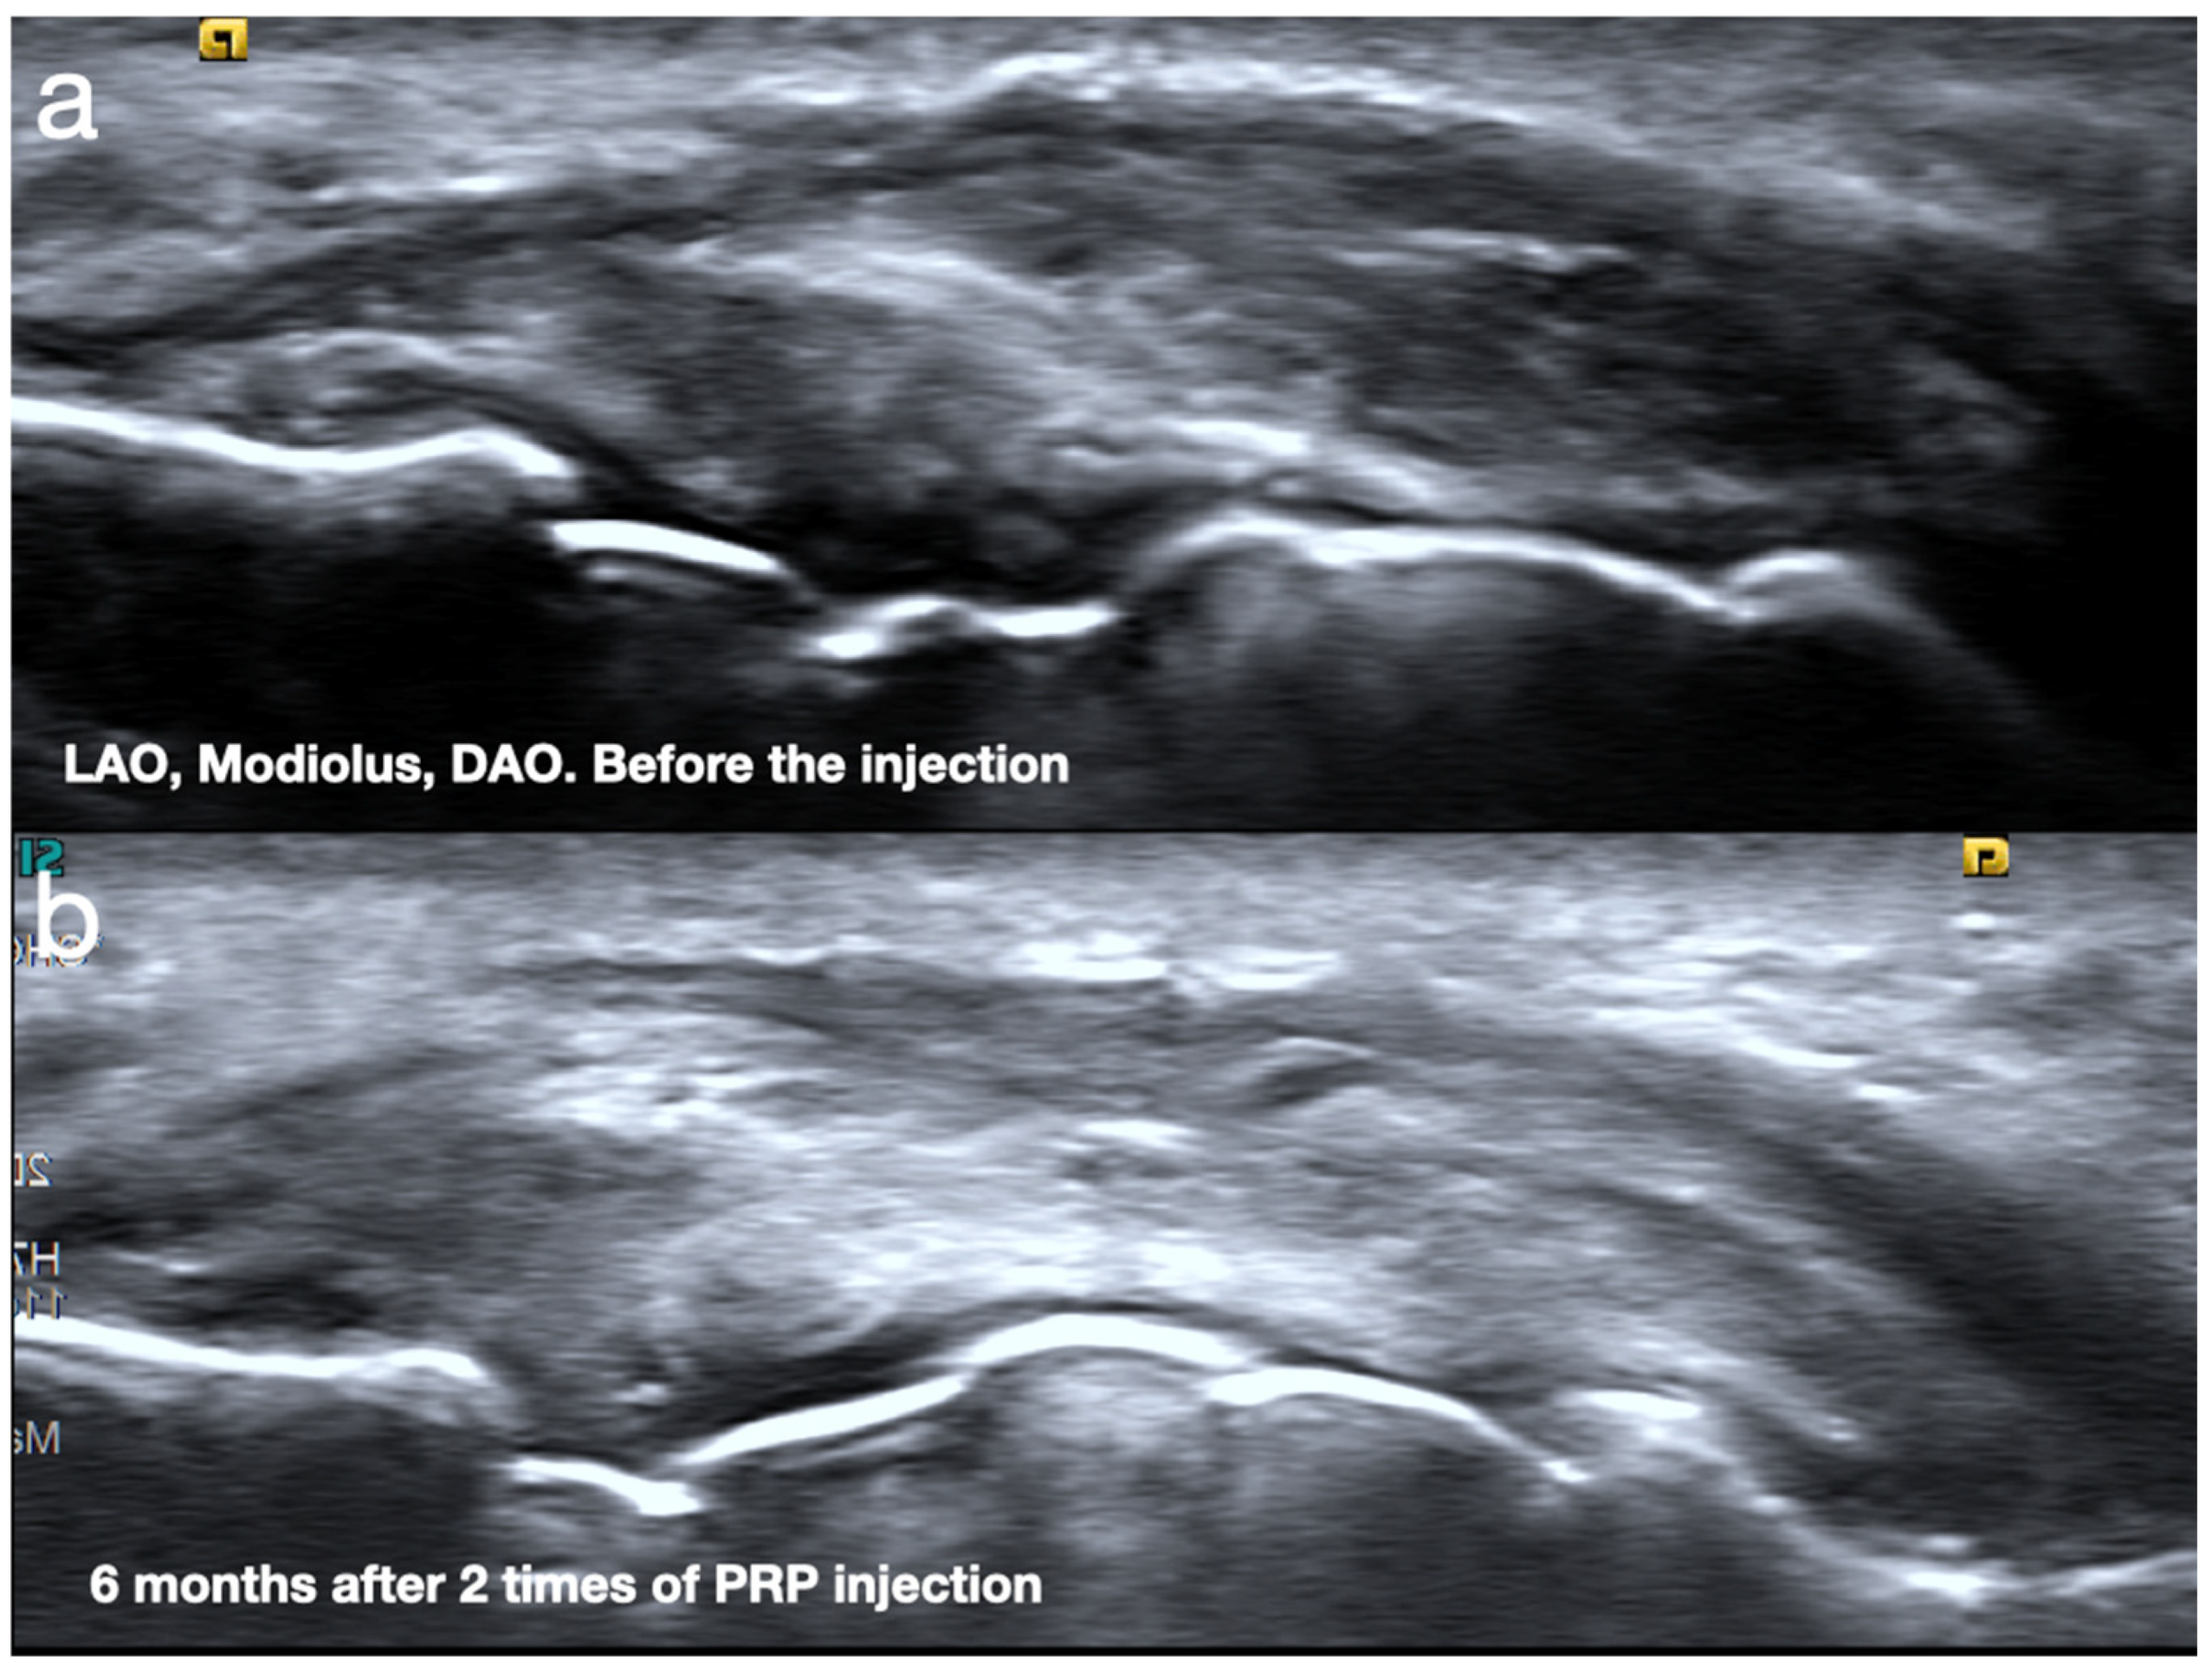

2.1. Sonoanatomy of Peri-Oral Musculature and Fascia System Concerning Embouchure

2.2. Scanning Protocol for the Embouchure in Wind Players

- Yeh, M.C.; Su, D.C.J. Using platelet rich plasma to treat embouhcure dysfunction, a case series. In Proceedings of the 42th Annual Conference of Performing Arts Association, London, UK, 18–21 July 2024. [Google Scholar]